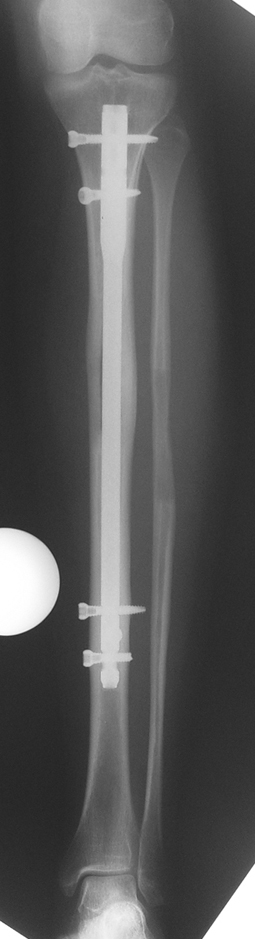

Biz son zamanlarda, seçilmiş vakalarda, uzatma sonrası uzunluğu ve “alignment’ı” korumak amacı ile unilateral dinamik aksiyel fiksatör ve kilitli intramedüller çivi kombinasyonunu tercih etmekteyiz. Bu yöntemin ön şartları medullanın en dar çapının 7 mm.’den geniş olması ve uzatma sonrası distalde en az 8 cm. uzunluğunda çivi kalabilmesidir. İntramedüller çivi hem uzatma esnasında femurun üzerine gelen makaslama ve bükülme kuvvetlerini nötralize etmekte hem eksternal fiksasyon süresini kısaltmakta, hem de yeni oluşan kemiği kırıklara karşı korumaktadır. Serimizde bir vakada subtrokanterik femoral osteotomi yapılmıştır. İntramedüller çiviye rağmen varus angulasyonu oluşması yönünde bir dezavantaj tespit etmedik.

Çocuklarda intramedüller çivi üzerinden uzatmanın bir diğer komplikasyonu olarak çivinin giriş yeri nedeni ile büyük trokanter apofizinin zedelenmesi ve sekonder koksa valga deformitesinin gelişmesi gösterilmektedir. Serimizdeki vakaların biri hariç tümü iskelet matüritesine erişmişlerdir. Oniki yaşında olan bir hastamızda son kontrolde koksa valga deformitesi saptanmamıştır. Vaka, halen takip edilmektedir.

İntramedüller çivi ve eksternal dinamik aksiyel fiksatör kombinasyonu teknik olarak standart İlizarov uygulamalarından daha zordur. Ancak şu avantajlar yöntemi cazip hale getirmektedir; eksternal fiksasyon süresinde kısalma, refraktüre karşı korunma, erken rehabilitasyon, azami hareket genişliği kazanma ve günlük yaşam konforu. Bu avantajlar artan maliyet , artan kan kaybı ve potansiyel derin infeksiyon gibi dezavantajların önüne geçmektedir. Sonuç olarak, bulgularımızın eşliğinde, intramedüller çivi üzerinden femoral uzatma tekniğinin güvenilir ve dayanıklı bir metod olduğunu ve bizce standart İlizarov uygulamalarına üstünlük sağlayan avantajlar getirdiğini söyleyebiliriz.